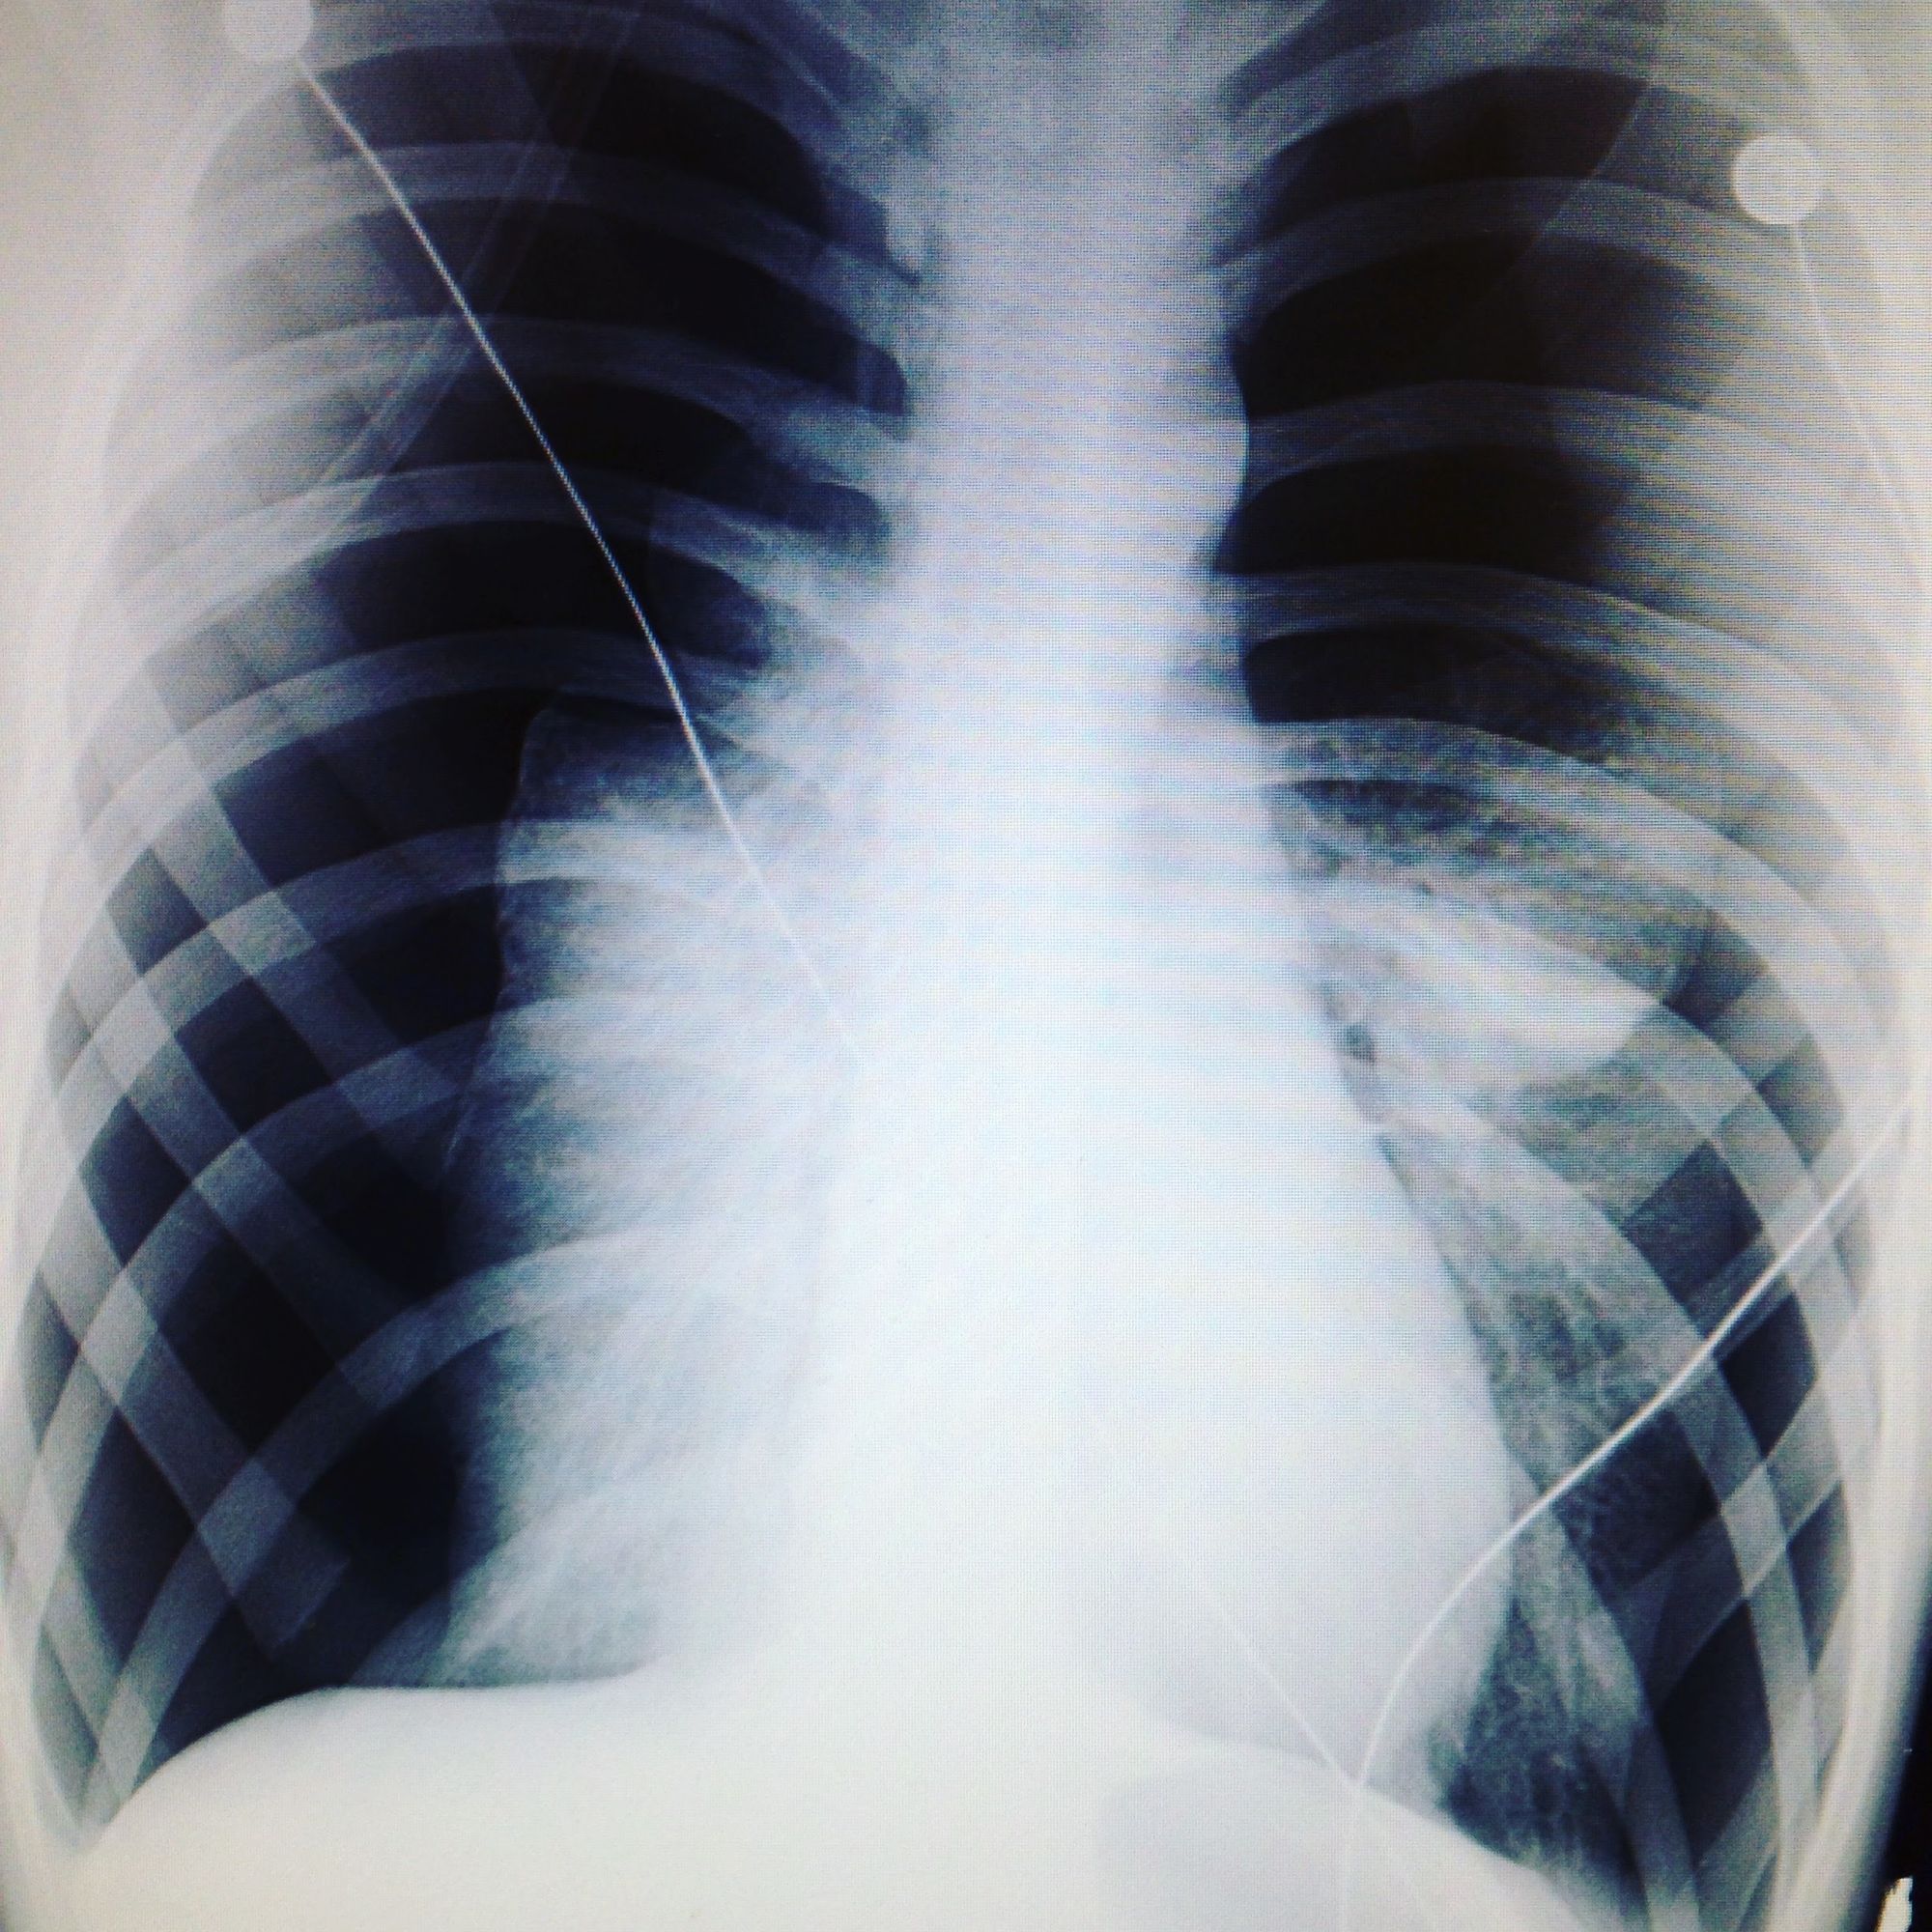

What you're seeing there are two collapsed lungs - Simultaneous Bilateral Spontaneous Pneumothorax. As far as I understand it, there was air or fluid in my rib cage preventing my lungs from inflating. There be more too it than that but I'm not a doctor ;)

According to one report I found online, 1 in 100,000 can suffer from a spontaneous collapsed lung but apparently only "1.3% of these cases can be bilateral (both lungs at once)", so pretty rare.

My condition was fairly progressed too, the doctor said had I left it a few more hours, it would have killed me.